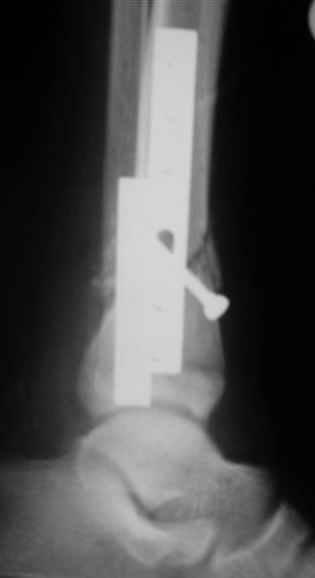

Помятуя наш недавний разговор о фиксации м.б. кост, высылаю послеоперационные картинки..

Напомню- разбирали случай 17 летнего молодого человека перелом дист тиб.фиб. хирургия после 3 недель с момента травмы( безуспешные попытки закрытой репозиции) Раны заживают первичным натяжением, занимается физиотерапией, пока никаких проблем не наблюдается

Как ты тут оцениваешь восстановление оси большеберцовой кости?

Является ли рутинной практикой у вас использовать снимок противоположной конечности как шаблон для измерения осевых отклонений?

Согласный я с тобой:-)) есть остаточная вальгусная деформация (по снимку видно перекрывание дист. фрагментом б.б по латеральной поверхности проксимальноо фагмента на 2-3 мм и наружная лодыжка репонирована с укорочением, судя по прямой проекции. Необходимость использования интраоперационно дистрактора была бы оправдана (вручную было непросто *вытянуть* дистальный отломок.)